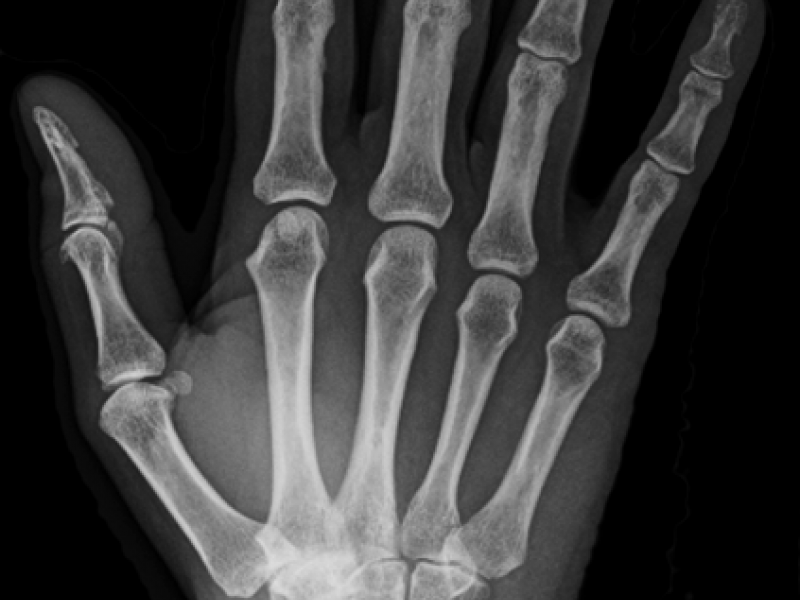

What's the Diagnosis? By Dr. Sarab Sodhi

A 53 y.o. female complains of pain in her right wrist after